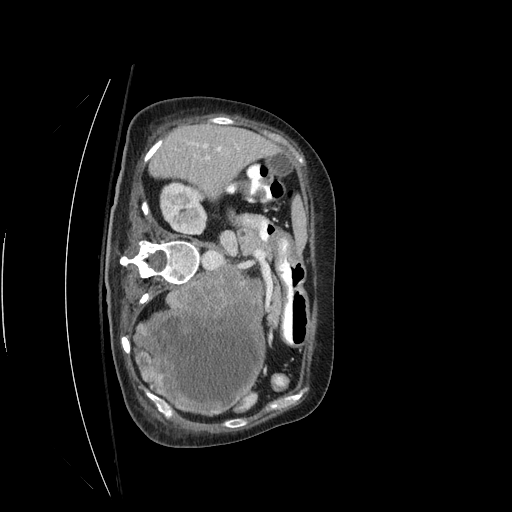

This challenge includes liver segmentation and liver tumor segmentation. The dataset consists of 131 training datasets and 70 testing datasets, all of which are 3D abdominal CT scan images that contain liver. Label maps (annotations) are provided for the training data, but not for the testing data. Participants are required to train their model on the training data, then use the well-trained model to make predictions for the testing data. The prediction can be submitted back to the orgnizer for blind evaluation. An example 3D CT data visualized in different directions is shown in Figure 5.

Refer to caption

Figure 5: Different positions of an example 3D CT data. Upper left: oblique coronal position. Upper right: add annotation (label) to the upper left image, where yellow area is the liver, green areas are the tumors on the liver. Lower left: sagittalia position; lower right: oblique-axial position.